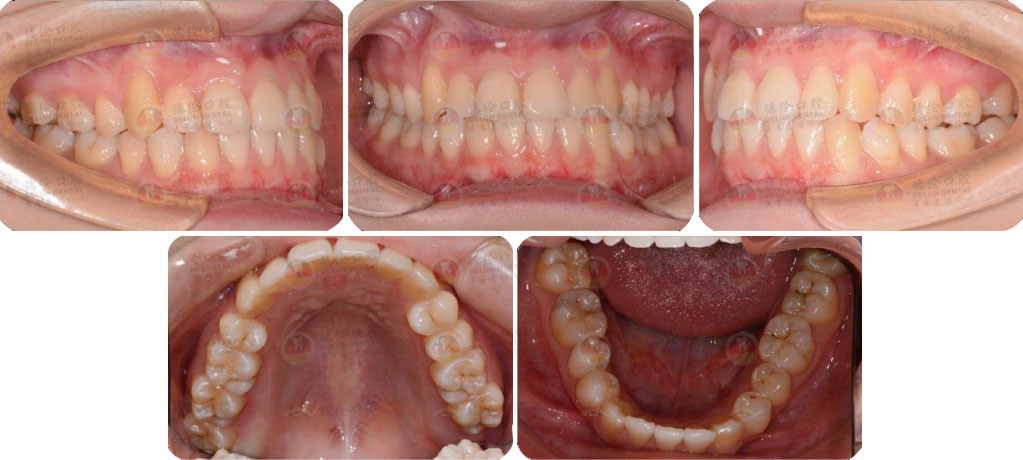

骨性I類,均角,安氏I類

上牙列重度擁擠,下牙列輕-中度擁擠

上中線右偏

13唇側錯位

• 【治療方案】

拔除14,排齊上牙列

下頜尖牙適當擴弓,配合適量鄰面去釉,排齊下牙列

上頜左側配合適量鄰面去釉,調整中線

盡量調整后牙為尖窩咬合關系

矯治前后對比

蛻變周期:上頜16個月,矯治效率提升30%,下頜12個月,矯治效率提升20%